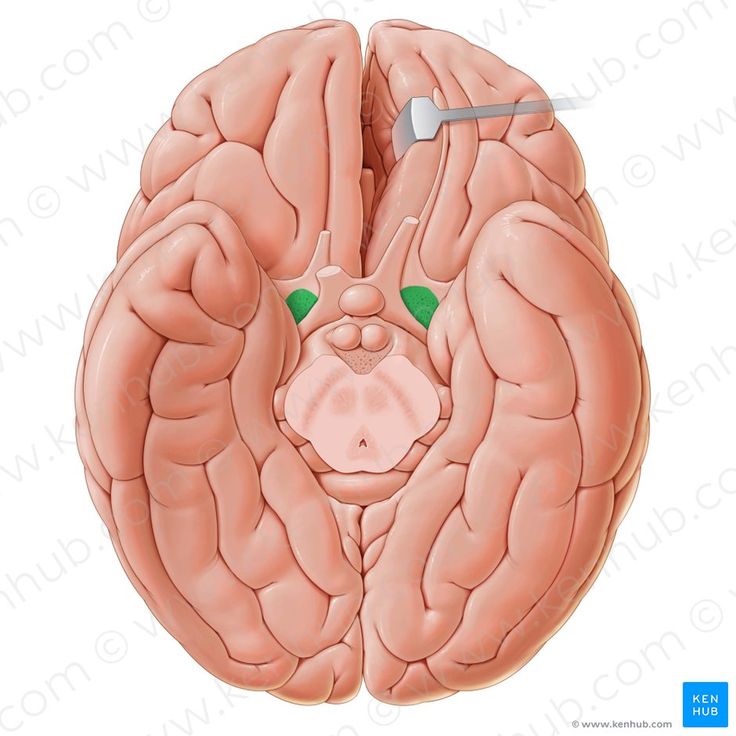

Необычные объекты: Переднее продырявленное вещество

Раздел: Альбом открытий